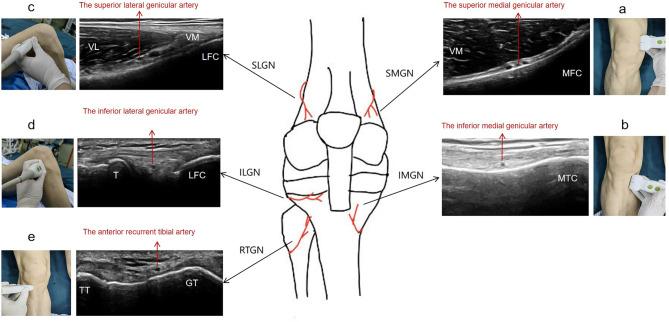

This randomized controlled and double-blind study aimed to investigate whether the analgesic effect of the adductor canal block (ACB) combined with the genicular nerve block (GNB) after total knee arthroplasty is noninferior to that of the adductor canal block combined with local infiltration analgesia (LIA).

A total of 102 patients undergoing total knee arthroplasty under general anesthesia were included and randomly divided into: ACB + GNB and ACB + LIA groups; the ACB + LIA group received 80 mL of 0.2% ropivacaine with adrenaline 10 µg/mL for LIA, whereas the ACB + GNB group received 4 mL of 0.2% ropivacaine for the blockade of five peri-knee nerves. The primary outcome was the median difference in the visual analog scale scores at rest at 24 h between the two groups. Secondary outcomes involved the median differences in the pain scores at other time points. Other outcomes included the cumulative dosage of opioids calculated in morphine equivalents in the first 24 h and indicators related to knee joint functional recovery.

纳入 102 例行全身麻醉下全膝关节置换术的患者,随机分为:ACB+GNB 组和 ACB+LIA 组;ACB+LIA 组接受 80 mL 含肾上腺素 10μg/mL 的 0.2%罗哌卡因行 LIA,而 ACB+GNB 组接受 4 mL 0.2%罗哌卡因用于阻滞膝关节周围 5 条神经。主要结局为两组患者术后 24 h 静息时视觉模拟评分(VAS)中位数差值。次要结局包括其他时间点疼痛评分的中位数差值。其他结局包括 24 h 内吗啡等效镇痛药物累积剂量和与膝关节功能恢复相关的指标。